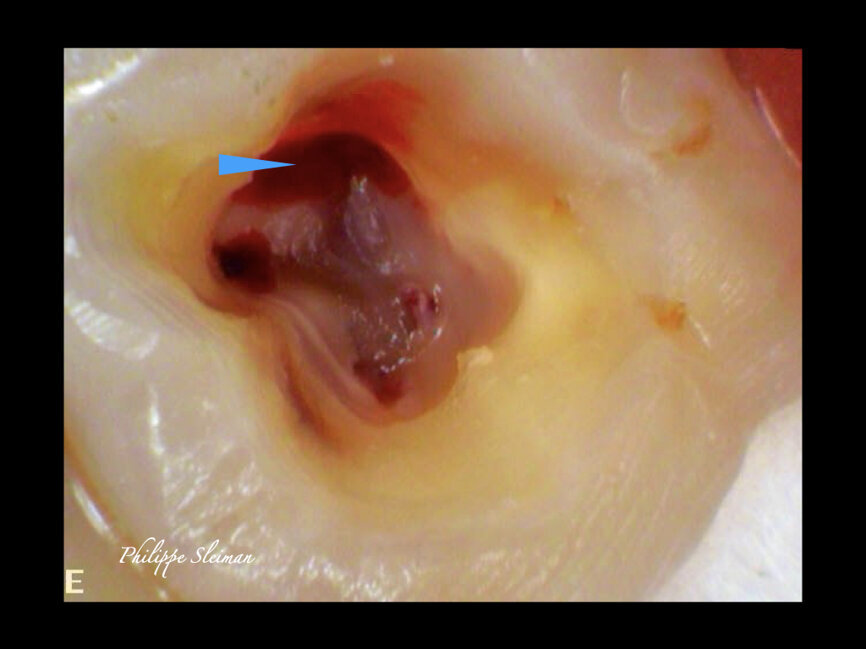

The preoperative radiograph and access cavity under the operating microscope (Images: Philippe Sleiman)

The preoperative radiograph (Fig. 1) revealed that the roots had an uncommon shape, particularly regarding the palatal root, the periodontal ligament and the apex of the mesial root. Upon creating the access cavity (Fig. 2), under the operating microscope, I noticed bleeding from the mesiopalatal angle. Extending the access cavity to that side led to the discovery of a separate canal, which may have been a second palatal or an independent mesial canal.